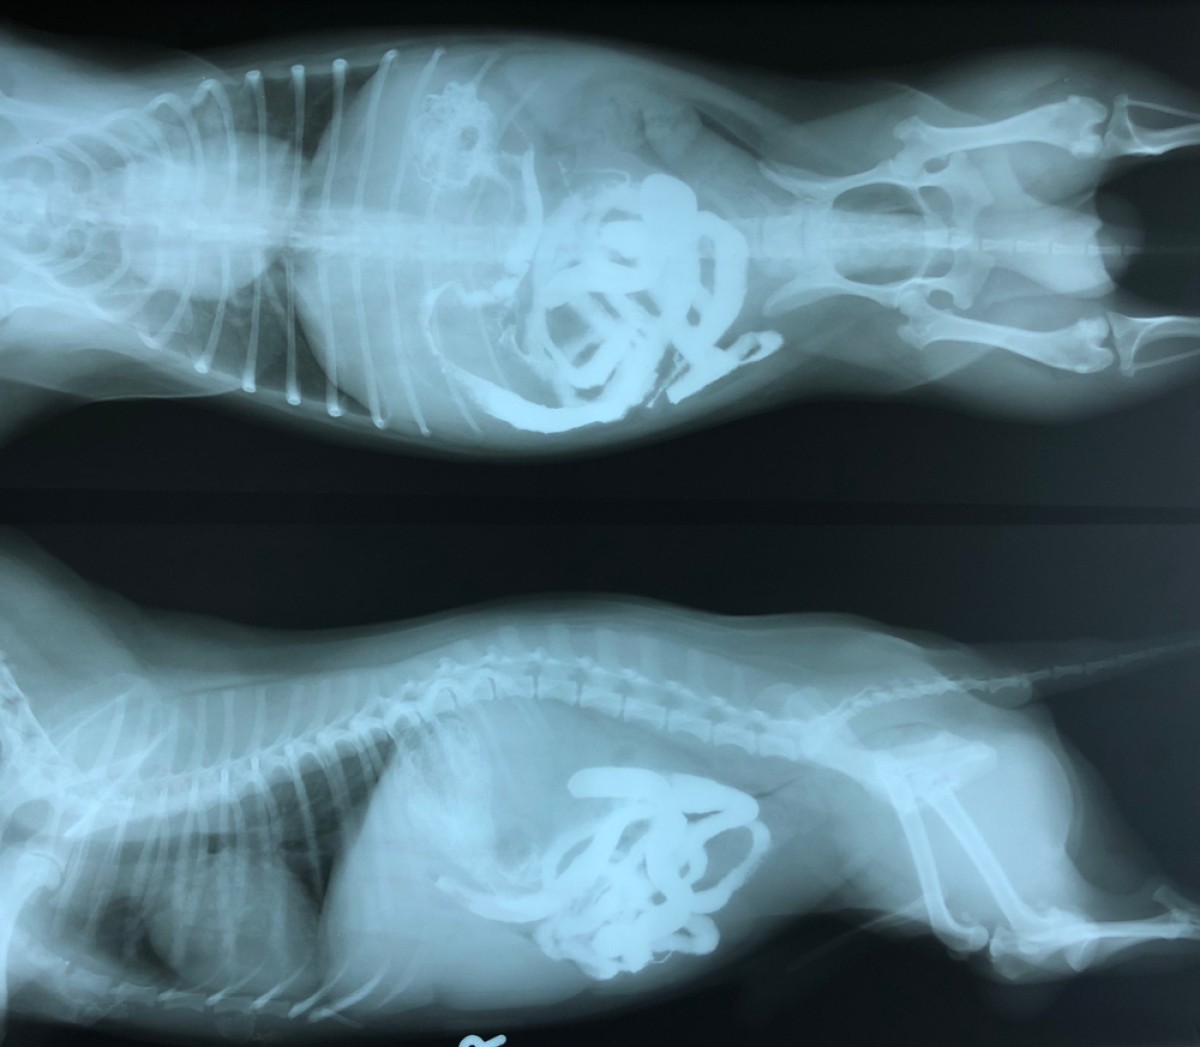

Les corps étrangers (CE) œsophagiens et gastriques sont fréquemment observés dans les cliniques traitant les petits animaux, et leur extraction endoscopique a déjà été rapportée. Cependant,...